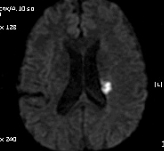

좌측사진은 PCA 영역. 우측사진은  AchA 영역의 post. periventricular corona radiata (Stroke 4ed p199, Fig 9-3 과 동일)

DWI coronal or saggital view 보면 분명하겠지만 이 사진으로 보니 PCA territory infarction으로 모두 설명되는 것 같습니다. PCA 영역에 hypoperfusion으로 병변이 크지는 것 같습니다. 5-7일 지나야 안정기에 들어갈 것 같습니다.